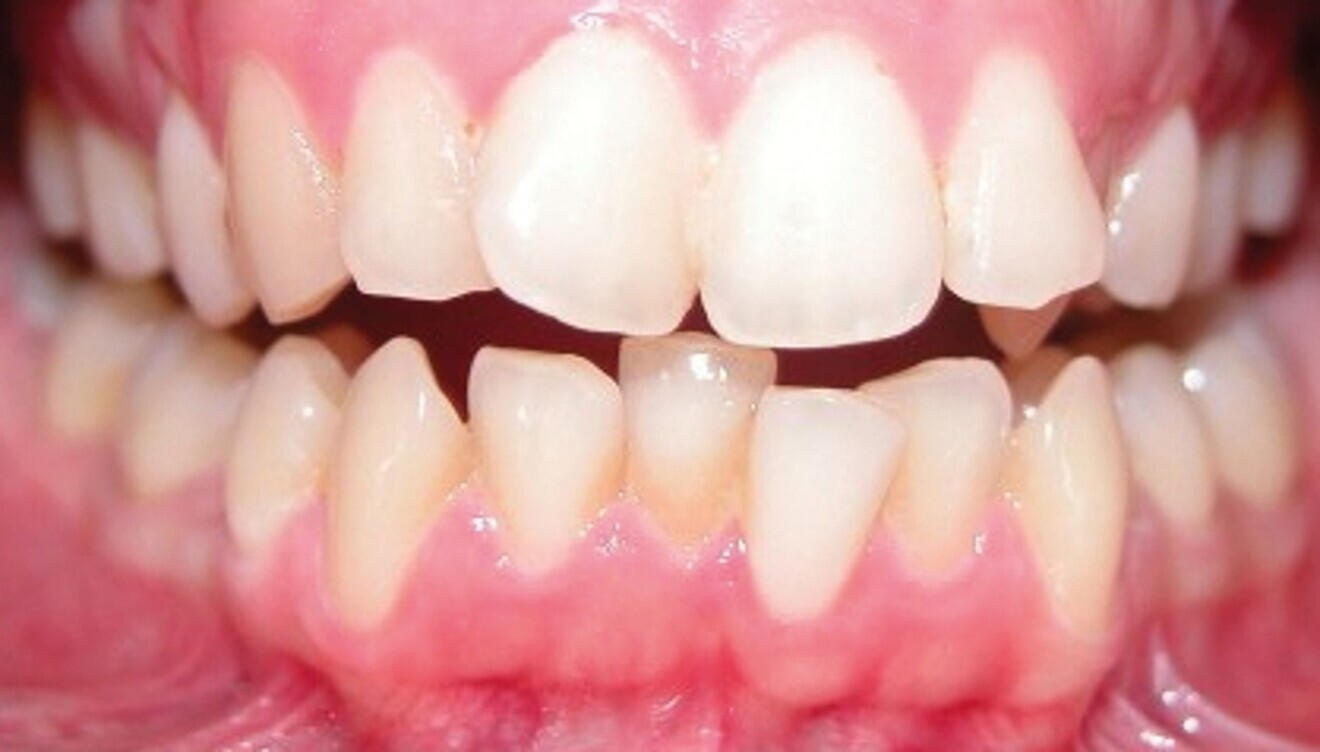

Le motif principal de consultation de la patiente, une jeune femme de 27 ans, est un encombrement dentaire accompagné d’une occlusion mal équilibrée. Danseuse de profession, elle se tracasse énormément au sujet de son apparence lors de ses apparitions publiques si elle entreprend un traitement. L’examen clinique révèle une relation d’Angle de classe I du côté droit et une relation molaire canine de classe II du côté gauche (Fig. 1).

De ce côté, les molaires, les prémolaires et la canine sont en occlusion croisée. L’examen ne montre aucun déplacement latéral fonctionnel de la mandibule. La ligne médiane maxillaire est en harmonie avec la symétrie faciale, mais la ligne médiane mandibulaire est déviée vers la gauche, en raison d’un décalage des dents de 4 mm. On observe un encombrement important des dents inférieures, évalué à 11 mm, et un encombrement modéré de 10 mm au niveau de l’arcade maxillaire. Les racines des dents 31, 33 et 43 semblent proches du rebord vestibulaire de l’os cortical, et les deux arcades présentent un rétrécissement dans la région des prémolaires et molaires.

Fig. 1b : Photographie intraorale initiale.